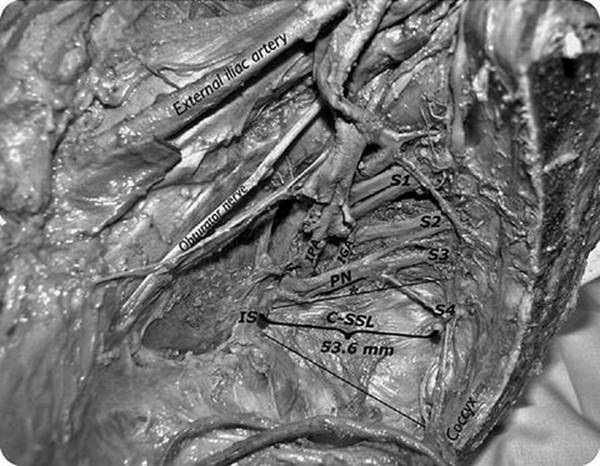

Significant hemorrhage is more common with sacrospinous colpopexy or hysteropexy than with other transvaginal apical repairs, largely due to the ligament’s delicate anatomic location. The sacrospinous ligament, running for about 5 or 6 cm [9] between the ischial spine laterally and the lateral border of the sacrum medially, forms the inferior border of the greater sciatic foramen, through which pass the superior gluteal vessels above the piriformis muscle, and the inferior gluteal and internal pudendal vessels below. The internal pudendal neurovascular bundle runs just inferior and medial to the ischial spine, and therefore suspension sutures should be sufficiently medial and superficial to these structures (Fig. 5.3). Similarly, dissection and suture placement should avoid the cephalad border of the sacrospinous ligament in order to minimize risk to the gluteal vessels and sciatic nerve. Although there is variation in the distance between the ischial spine and pudendal nerve and vessels and the sciatic nerve [10], in general these structures can be avoided by placing suspension sutures in the middle or medial third of the ligament, avoiding the cephalad border of the ligament, and placing sutures through the ligament alone, and not deep through the underlying coccygeus muscle.

Fig. 5.3

Sagittal cadaveric dissection demonstrating the relationship of the coccygeus-sacrospinous ligament (C-SSL) to the sacral nerve roots and pudendal nerve (PN). Important vascular structures include the internal pudendal artery (IPA) and the more medial inferior gluteal artery (IGA). Source: Roshanravan et al. [28]

Knowledge and understanding of the nearby anatomy is essential. Suture placement in the middle third of the sacrospinous ligament avoids the region of the pudendal nerve, and staying caudad to the greater sciatic foramen avoids the sciatic nerve [10]. Anatomic studies also reveal, however, that nerves to the coccygeus and levator ani actually pass ventral to the ligament in the middle segment, where sutures are typically placed, and may be encountered during dissection and suture placement [28]. Histologic studies of the ligament itself confirm nerves within the substance of the ligament, especially in the middle segment [29], which explains the potential for pain after this operation. In fact, another cadaveric study found the only nerve-free region of the ligament to be the medial third [30], which is more medial than is often described in the operation.